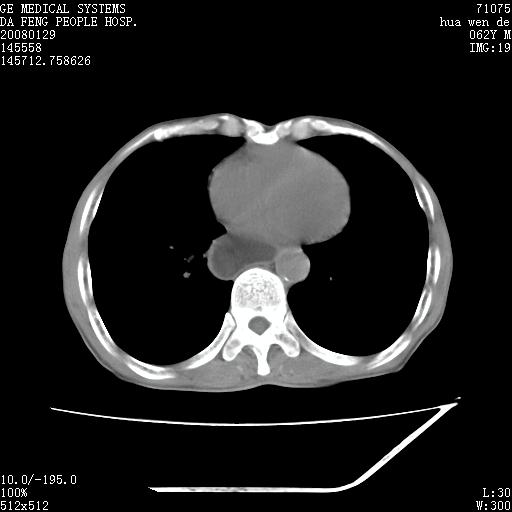

男性,67岁。作肺部检查时发现

1.整个食管扩张,未见明显占位性病变,贲门区亦未见明显占位病变,考虑:贲门失驰缓症;

2.右上肺病变边缘可见毛刺,囊壁厚度不均匀,周围境界较清楚,未见炎性渗出性影,右上肺外带可见片状影,边缘不清,考虑:肺癌伴空洞形成、右上肺炎。

15楼主分析有道理,胸腔胃除外,那么考虑贲门失驰缓症并肺部化脓感染(吸入性)可能。

肺内病灶位于右肺中叶,食道扩张后导致咽部功能受影响,吸入气管可能是存在的。

可疑之处在于:左肺未见吸入性病灶存在。另右肺癌(右肺中央型并阻塞性肺炎)不能除外

食管全程扩张,壁均匀不厚,喷门失弛缓症

右上肺空洞可见液平,临近肺野磨玻璃密度,考虑1.结核2.脓肿